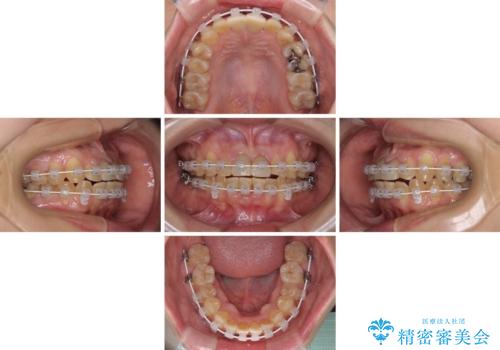

前歯のデコボコをワイヤー矯正できれいに整える

- 矯正装置

- 審美装置

抜歯矯正により口元を引っ込めることも検討しましたが、特に口元の突出感は気になっていないとのことで、非抜歯にてワイヤー装置で矯正治療を行うこととしました。

舌の突出癖により治療期間中に開咬となり、治療が長引きましたが、口元も治療前よりも引っ込めることができ、すっきりとした仕上がりとなりました。